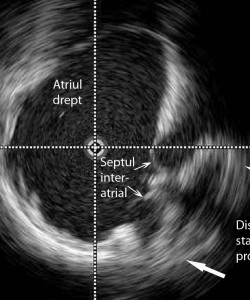

În data de 23 noiembrie 2015, în cadrul Cardiostructural Clinic din Spitalul Monza din Bucureşti au fost efectuate cu succes primele proceduri endovasculare ghidate prin ecocardiografie intracardiacă. Echipa medicală a Centrului de Intervenţii Structurale Cardiovasculare constituită din Dr Şerban Bălănescu, Dr Adrian Linte şi Dr Andrada Bogdan cu suportul tehnic al Dr Eustaquio Onorato de la Clinica Humanitas Gavazzeni, Bergamo, au realizat tratamentul endovascular cu închiderea unui defect septal atrial la o pacientă în vârstă de 49 ani şi a unui foramen ovale patent la o pacientă în vârstă de 17 ani, care a suferit un accident vascular cerebral ischemic recent.

Ecocardiografia intracardiacă este o metodă imagistică în timp real care constă în vizualizarea imaginilor ecocardiografice cu ajutorul unei sonde introduse în interiorul cavităţilor cardiace pe calea venei femurale şi a venei cave inferioare. Aplicabilitatea practică a ecocardiografiei intracardiace se regăseşte în sala modernă de cateterism cardiac în timpul efectuării unor proceduri complexe de corectare a unor anomalii cardiace structurale, mai ales congenitale. Dintre acestea cele mai importante sunt defectul septal atrial, foramenul ovale patent, defectul septal ventricular sau stenoza aortică.

1_defect_septal_atrial_eco_intracardiac